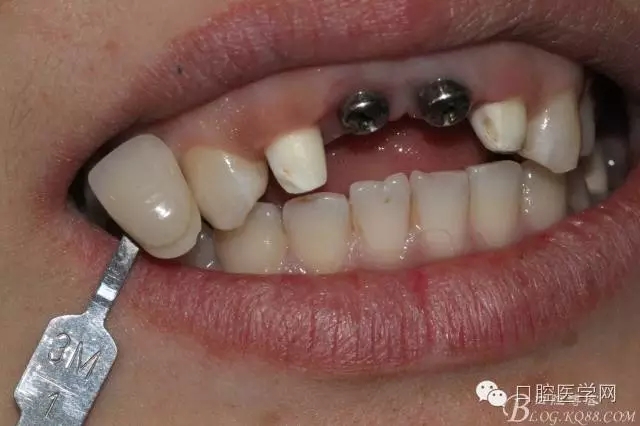

比色

因該患者笑線比較高,不微笑也露出牙齦,所以考慮到美觀,兩顆中切齒上方給做的牙齦瓷。